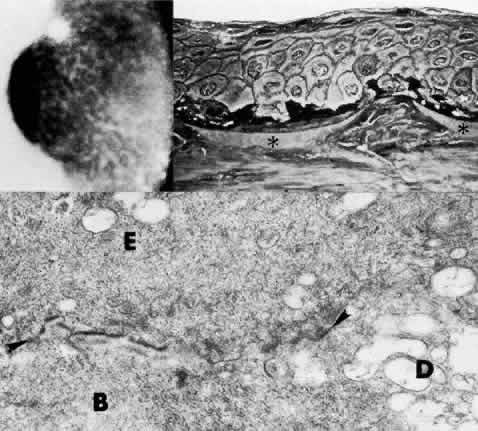

Fig. 8. Reis-Bucklers dystrophy. Top left. Slit lamp photograph of eye of 26-year-old woman with recurrent erosions exhibits typical superficial reticular opacities. Top right. Phase-contrast microscopy demonstrates degeneration of dark-staining basal cells and fragmentation of Bowman's layer (*) by nodular fibrous pannus (paraphenylenediamine, × 800). Bottom. Transmission electron micrograph confirms thin remnants of disarrayed Bowman's layer (B) and apparent continuity (at arrowhead) between basal cell cytoplasm (E) and degenerate cellular debris (D) within Bowman's layer. Basement membrane complexes are discontinuous and lack anchoring fibrils (× 30,000).

The pathogenesis of Reis-Bucklers dystrophy is unknown. The primary lesion may be due to fragmentation of the collagen fibrils of Bowman's layer, and the epithelial lesion may occur secondarily.85 Alternatively, immunofluorescent localization of laminin and bullous pemphigoid antigen suggests a primarily epithelial disease.86 Destruction of Bowman's layer and its replacement by fibrillar material are the defining changes in this disease and unequivocally distinguish it from other anterior dystrophies. Concomitant abnormalities in the epithelial basement membrane account for recurrent erosive episodes.49,87–91